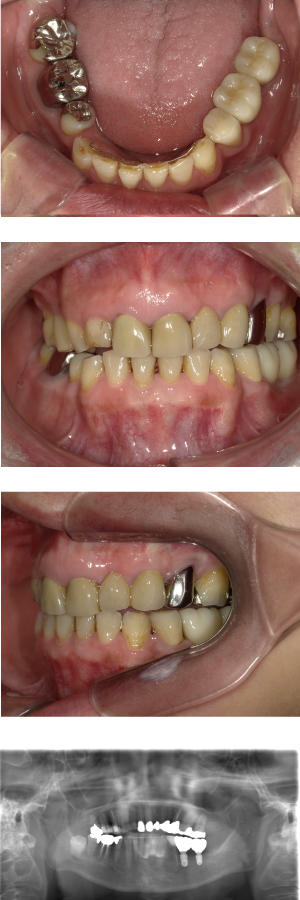

50代 インプラント治療(右上3左上3のみGBR)

| 年代・性別 | 50代・男性 |

|---|---|

| 主訴 | 入れ歯が合わず毎日ヨーグルトしか食べることができないので、しっかり咬めるインプラントにしたい。 |

| 部位 | 右下⑦⑥5④ 上顎③2①①2③ 左下67 |

| 治療期間 | 約9ヶ月 |

| 費用 | ¥4,273,500(税込) |

| 副作用・リスク |

|